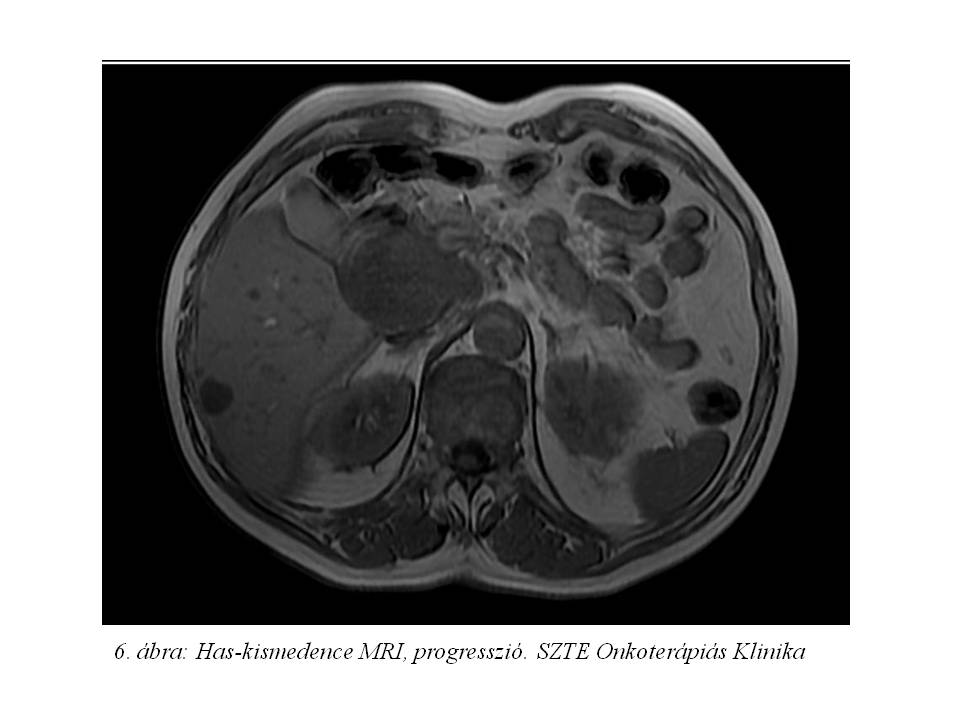

2015.01.06-án készült has-kismedence MR vizsgálat (6. ábra) a máj áttétek méretbeli és számbeli progresszióját, valamint a pancreas fej követett folyamatának ismételt növekedését mutatták. A beteg gastrin és chromogranin szintje végig normál tartományban volt.